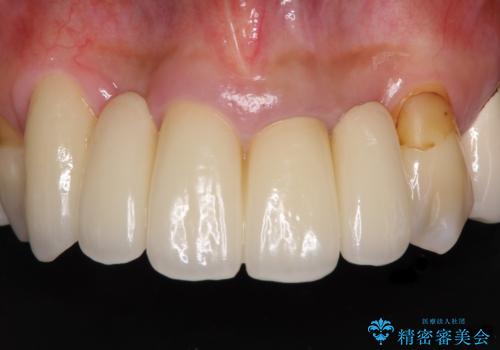

高さの足りない奥の銀歯をセラミッククラウンに

- 奥歯の銀座を白くしたいとのことで来院された患者様です。

右下の奥歯は、土台の高さが足りずセラミッククラウンを装着することが困難であったため、歯冠長延長術と歯肉弁根尖側移動術を行い、十分な土台の高さと角化歯肉幅を獲得することとしました。

治療終了時に、治療前との比較写真をご覧いただいたところ、土台の高さが十分に増したことに驚かれ、その結果として銀歯がなくなったことで審美面が改善されたことに大変満足していただけました。